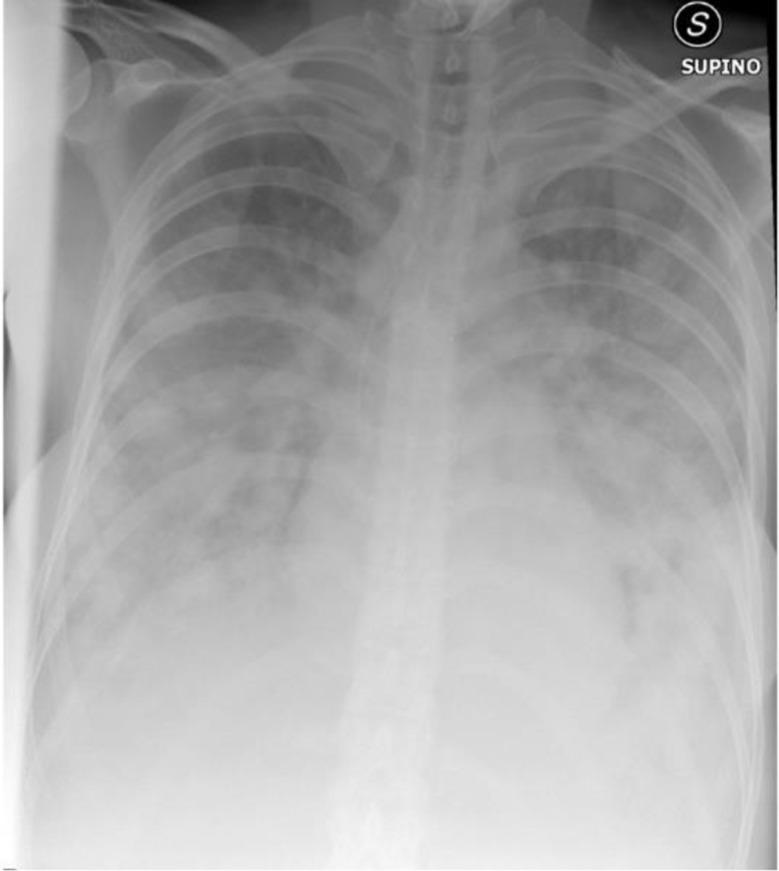

We describe the case of a patient with acquired immunodeficiency syndrome (AIDS) with rapidly worsening dyspnoea and clinical signs suggestive of acute respiratory distress syndrome (ARDS). Despite initial concerns for ARDS, autopsy revealed an advanced-stage, aggressive lymphoma as the underlying cause. This case highlights the challenge of differentiating ARDS from lymphoma in AIDS patients, especially when atypical radiologic findings, such as nodular opacities, are present.

我们描述了一例获得性免疫缺陷综合征(AIDS)患者的病例,该患者呼吸困难迅速加重,并有提示急性呼吸窘迫综合征(ARDS)的临床体征。尽管最初怀疑是ARDS,但尸检显示潜在病因是晚期侵袭性淋巴瘤。该病例突出了在艾滋病患者中区分ARDS和淋巴瘤的挑战,特别是当出现如结节状混浊等不典型放射学表现时。